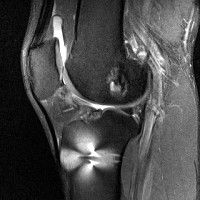

무릎 mri 간단히 봐주실 수 있으시나요 ㅠㅠ

안녕하세요 8년전 십자인대 수술하고 최근 무리한 운동에 무릎 불편감이 생겨서

mri 찍었습니다.

진단결과는 첫 찍은 병원에서 활액막염 이라는 진단을 받았습니다. 혹시 봐주실 수 있으실까요?

올라온 MRI가 단편적이라서 정확한 진단에 어려움이 있지만 십자인대에는 큰 이상이 있지는 않은것 같으며, 무릎관절내 물이 있는 것으로 보아 활액막염의 진단이 맞을 것 같습니다.

하지만 단편적인 영상이기 때문에 촬영병원에서 정확한 판독지 등을 받으시는 것이 좋겠습니다.